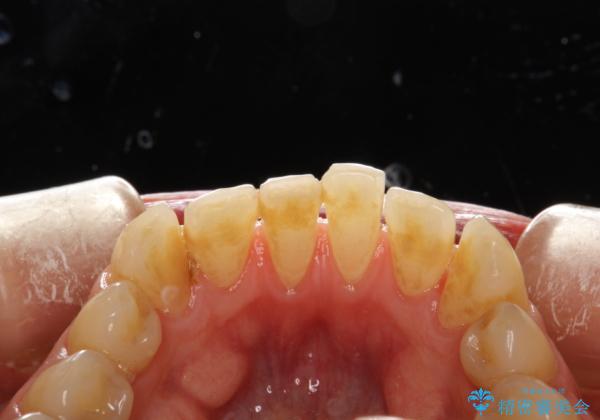

歯磨き中に血が出る PMTCで歯石除去

- 毎日の歯磨きの際に出血する。歯科でにクリーニンングをしばらくしていないとのことでした。PMTC60分コースを行いました。

歯磨きの際の出血は、歯肉炎や歯周病の症状とも言えます。歯周ポケットに歯周病菌が棲みつき、歯周病菌の出す毒素が歯茎に炎症を起こします。炎症が拡大し、歯周組織が破壊されたまま放置すると、最悪の場合、歯を支えている骨が溶かされ、歯がぐらぐらしてきます。